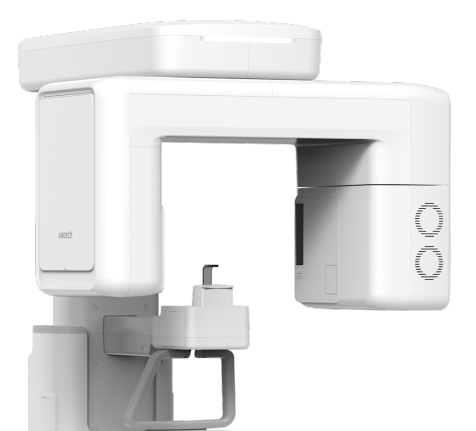

| CBCT | PANO | CEPH | |

|---|---|---|---|

| Vatech A9 | | | |

| Vatech A9 RC | | | |